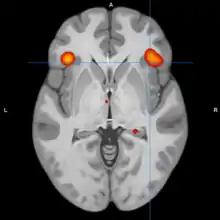

Bipolar disorder is an affective disorder characterized by periods of elevated and depressed mood. The cause and mechanism of bipolar disorder is not yet known, and the study of its biological origins is ongoing. Although no single gene causes the disorder, a number of genes are linked to increase risk of the disorder, and various gene environment interactions may play a role in predisposing individuals to developing bipolar disorder. Neuroimaging and postmortem studies have found abnormalities in a variety of brain regions, and most commonly implicated regions include the ventral prefrontal cortex and amygdala. Dysfunction in emotional circuits located in these regions have been hypothesized as a mechanism for bipolar disorder.[1] A number of lines of evidence suggests abnormalities in neurotransmission, intracellular signalling, and cellular functioning as possibly playing a role in bipolar disorder.[2]

A model of functional neuroanatomy produced by a workgroup led by Stephen M. Strakowski concluded that bipolar was characterized by reduced connectivity, due to abnormal pruning or development, in the prefrontal-striatal-pallidal-thalamic-limbic network leading to dysregulated emotional responses. This model was supported by a number of common neuroimaging findings. Dysregulation of limbic structures is evinced by the fact that hyperactivity in the amygdala in response to facial stimuli has been consistently reported in mania.[33] While amygdala hyperactivity is not a uniform finding, a number of methodological challenges could explain discrepancies. As most studies utilize fMRI to measure blood-oxygen-level dependent signal, excess baseline activity could result in null findings due to subtraction analysis. Furthermore, heterogenous study design could mask consistent hyperactivity to specific stimuli. Regardless of directionality of amygdala abnormalities, as the amygdala plays a central role in emotional systems, these findings support dysfunctional emotional circuits in bipolar. A general reduction in ventrolateral prefrontal cortex activity is observed in bipolar, and is lateralized with regard to mood (i.e., left-depression, right-mania), and may underlie amygdala abnormalities. The dorsal ACC is commonly under-activated in bipolar, and is generally implicated in cognitive functions, while the ventral ACC is hyperactive and implicated in emotional functions. Combined, these abnormalities support the prefrontal-striatal-pallidial-thalamic limbic network underlying dysfunction in emotional regulation in bipolar disorder.[34] Strakowski, along with DelBello and Adler have put forward a model of "anterior limbic" dysfunction in bipolar disorder in a number of papers.[35][36][37][38][39]

Blond et al. proposed a model centered on dysfunction in an "amygdala-anterior paralimbic" system. This model was based on the consistent functional and structural abnormalities in the ventral prefrontal cortex and amygdala. The model also proposes a developmental component of bipolar disorder, wherein limbic abnormalities are present early on, but rostral prefrontal abnormalities develop later in the course. The importance of limbic dysfunction early in development is highlighted by the observation that amygdala lesions early in adulthood produce emotional abnormalities that are not present in people who develop amygdala damage in adulthood.[41]

Studies examining resting blood flow, or metabolism generally observed abnormalities dependent upon mood state. Bipolar depression is generally associated with dlPFC and medial orbitofrontal cortex hypometabolism. Less consistent associations include reduced temporal cortex metabolism, increased limbic metabolism and reduced ACC metabolism. Mania is also associated with dlPFC and OFC hypometabolism. Limbic hypermetabolism is more consistent than in bipolar depression, but the overall study quality is low due to limitations associated with neuroimaging in acutely manic patients.[70] Another review reported that mania is generally associated with frontal/ventral hypoactivation, while depression is generally associated with the opposite. A degree of lateralization with regard to abnormalities has been reported, with mania being associated with the right hemisphere, and depression the left. Trait abnormalities in euthymic patients have been observed, including hypoactivity in the ventral prefrontal cortex, and hyperactivity in the amygdala.[71]

During cognitive or emotional tasks, functional neuroimaging studies, consistently find hyperactivation of the basal ganglia, amygdala, and thalamus. Prefrontal abnormalities are less consistently reported, although hyperactivation in the ventral prefrontal cortex is a fairly consistent finding.[72] Hyperactivity in the amygdala and hypoactivity in the medial and ventral prefrontal cortex during exposure to emotional stimuli has been interpreted as reflecting dysfunction in emotional regulation circuits. Increased effective connectivity between the amygdala and orbitofrontal cortex, and elevated striatal responsiveness during reward tasks have been interpreted as hyper-responsiveness in positive emotion and reward circuitry. The abnormal activity in these circuits has been observed in non-emotional tasks, and is congruent with changes in grey and white matter in these circuits.[73] Neural response during reward tasks differentiates unipolar depression from bipolar depression, with the former being associated with reduced neural response and the latter being associated with elevated neural response.[74] An ALE meta analysis of functional neuroimaging comparing adults and adolescents found a larger degree of hyperactivity in the inferior frontal gyrus and precuneus, as well as a larger degree of hypoactivity in the anterior cingulate cortex in adolescents relative to adults[75]